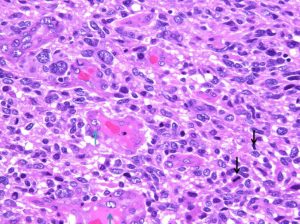

偽柵状配列の周辺部の拡大所見。chromatinに富む核の腫大と多態性(→)を示す腫瘍細胞と血管(V)の増加が見られる。

HE x200

腫瘍細胞核の多態性と血管内皮細胞核の腫大(青↑)および核分裂像(黒↓)が認められる。

HE x400